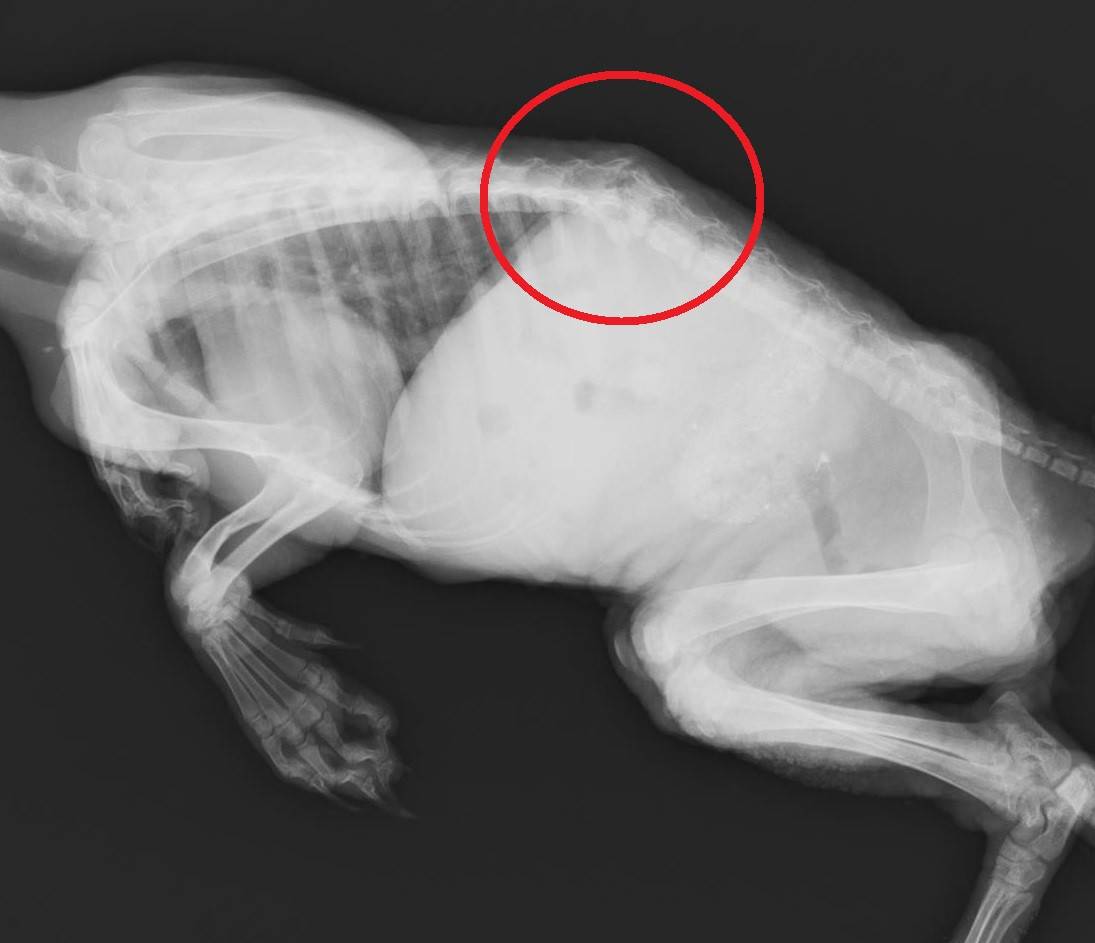

このタヌキは起立不能な状態で保護されました。このような場合は脊椎に異常があることが多いのでレントゲン検査で確認することに。

やはり、脊椎に異常が。腰椎を骨折しておりました。個体の状態はあまりよくありませんが、急を要するため、すぐに手術を行う事になりました。骨折部の骨を少し削り、脊髄が圧迫されない様な処置を行ったうえで医療用のピンを使って固定することにしました。